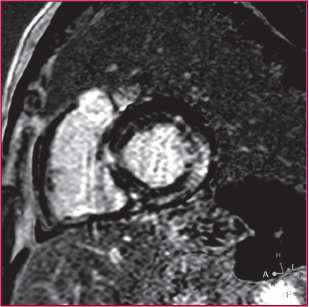

Se realizó una resonancia magnética cardíaca donde se observó moderada dilatación biauricular con función sistólica de ventrículos izquierdo y derecho global deprimida en grado leve (FEy: 50% y 46%, respectivamente), sin derrame pericárdico ni pleural, con realce tardío a los 10 minutos posteriores a la administración de material de contraste (gadolinio) en los niveles intramiocárdico y subepicárdico difuso, con predominio de los segmentos basales y a el nivel auricular (patrón no isquémico), compatible con amiloidosis cardíaca como diagnóstico presuntivo (Figura 1).

El patrón habitual consiste en un realce subendocárdico y general (que no compromete a un territorio coronario, como se observa en la cardiopatía isquémica). (1) Existen otros patrones que podrían relacionarse con la evolución de esta enfermedad, donde se observa de modo parcheado, localizado o transmural (2), como en el caso que se presenta.